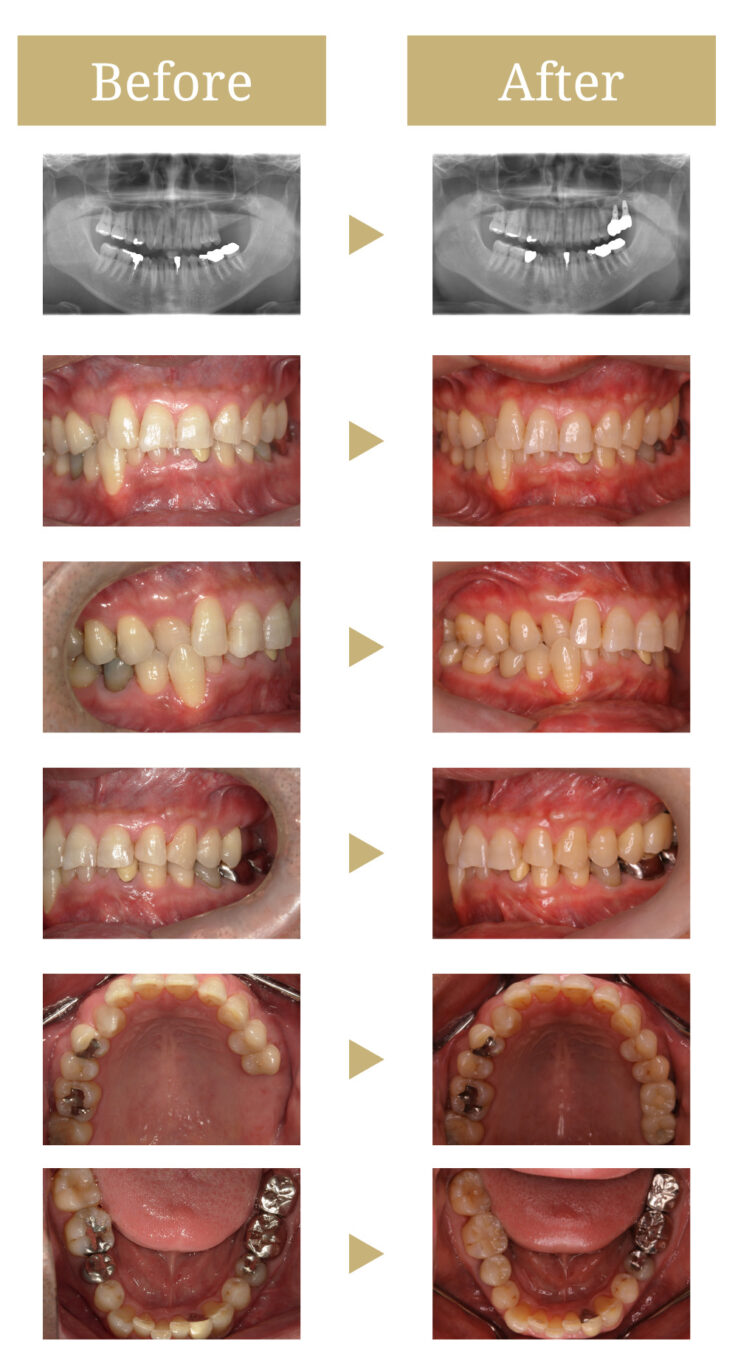

上顎臼歯部骨吸収に対してサイナスリフトを併用したインプラント補綴症例

上顎洞底部の骨吸収が進行しており、既存骨量ではインプラント埋入が困難と判断しました。

そのため、サイナスリフト(上顎洞底挙上術)を併用したインプラント治療をご提案。

左上6番・7番部に2本のインプラントを埋入し、最終的にブリッジ形式で補綴する計画としました。

左上6番・7番相当部にインプラントを同時埋入しました。

約6か月のオッセオインテグレーション期間(インプラントと骨を結合させる期間)を経て、印象採得を行い、最終補綴としてジルコニアクラウン(連結タイプ)を装着しました。

治療前の状態

左上6・7番欠損部は骨吸収が進行し、上顎洞底までの残存骨高径は5mm未満でした。

咬合支持が失われ、対合歯の挺出傾向がありました。

治療後の状態

サイナスリフト部の骨再生は良好で、インプラントの安定性も高く、骨吸収や透過像はありませんでした。

最終補綴装着後は咬合バランスが改善し、良好な咀嚼機能が回復。審美性にも優れ、患者様にもご満足いただけました。